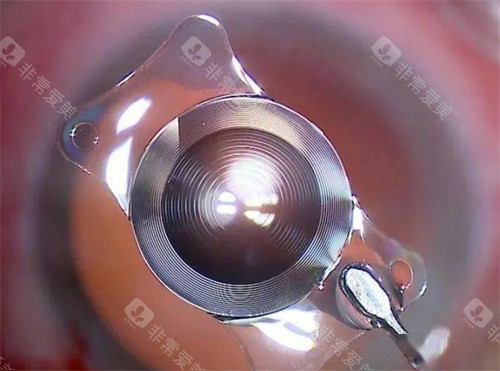

医院采用的手术方式主要有超声乳化白内障吸除术联合人工晶状体植入术等,这些手术方式具有切口小、改善快等优点。

不同的白内障手术方式和人工晶状体等材料的价格差异较大,这会直接影响报销金额。

一些高端的手术方式和进口的人工晶状体价格较高,虽然部分费用可以报销,但报销后患者仍需承担较大的自费部分。

而选择一些性价比高的国产材料和常规手术方式,报销后患者的自费金额相对会少一些。